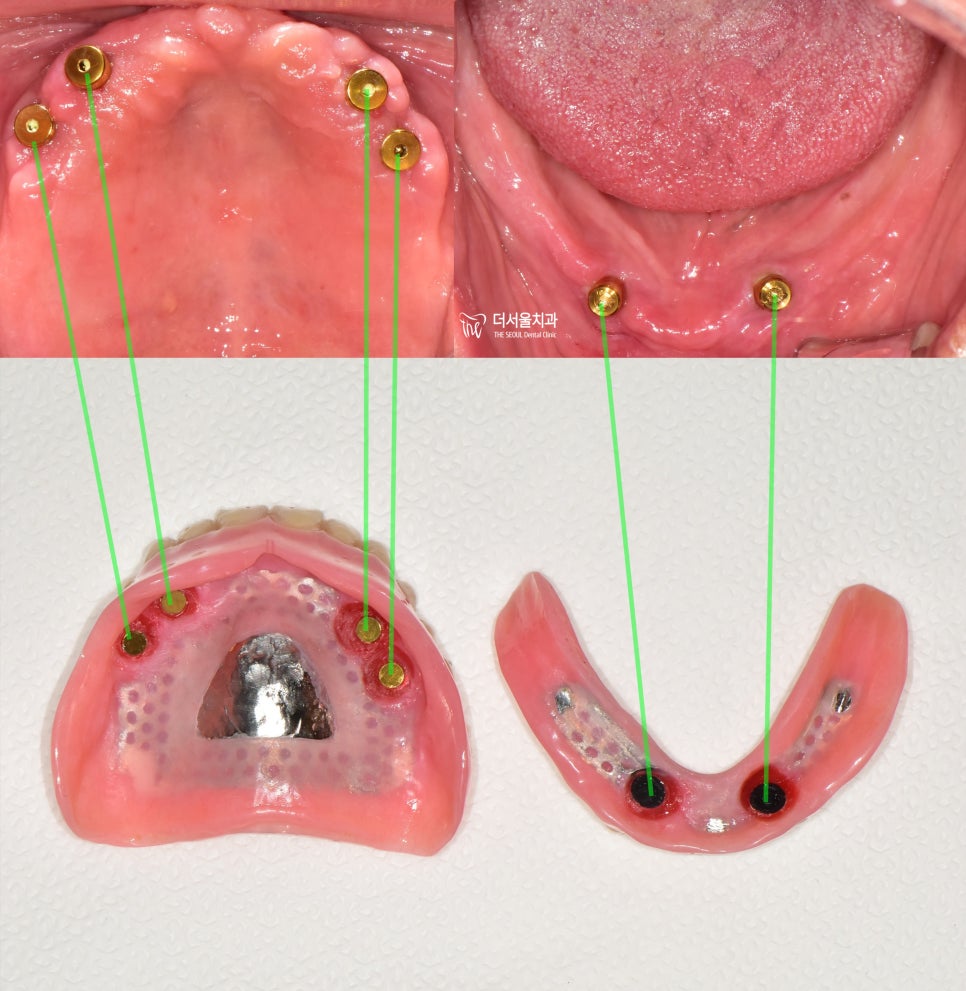

구강 내 심겨진 attachment 들과

임플란트 틀니 내면에 심겨져 있는 버튼들과

서로 결합을 통해서 유지력을 얻게 됩니다.

전문..용어로는

male part 와 female part 의

결합이라 부릅니다.

attachment 의 형태는

치과마다 조금씩 다릅니다.

1) 볼 타입

2) 자석 타입

3) 똑딱이 타입

등이 있는데 각기 다른 장점이 있으니

이건 담당 주치의와 상담하면 됩니다.